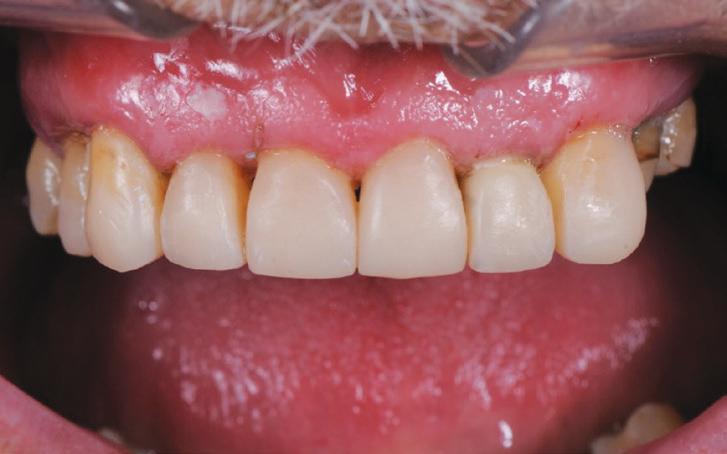

AFTER

Natural colours and a beautiful, life-like surface polish were produced with the multilayered application of this nanocomposite – HarmonizeTM (Fig. 19).

Importantly, the stability of the occlusion was re-established with creation of occlusal contacts on each tooth, and the re-introduction of canine and incisal guidance, to control lateral and protrusive forces (Figs. 20, 21, 22, 23).

Treatment Outcome

The functional and aesthetic results of the treatment are evident in the post-treatment photographs. This gentleman was able to have a full mouth rehabilitation completed in composite resin, achieving the desired improvements in the appearance of his smile, and the return of stability to his dentition, all within a cost that he could afford, by using direct restorative procedures instead of conventional crown and bridgework. This treatment was made